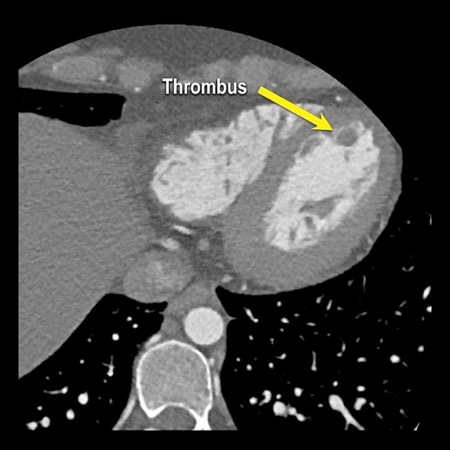

case 4 – CAD-RADS 3/P1/I+ thrombus left ventricle

The findings are:

- Moderate (50-69%)

stenosis in the proximal LAD caused by a non-calcified plaque. - Variant of

sinoatrial (SA) nodal artery. The artery usually arises from the RCA as a second

branch after the conus artery, however in this case it arises from the LCX,

courses behind the aorta, anastomosing with the right atrium and with a small

branch supplies the SA-node of the heart. - Thrombus in the

apex of the left ventricle. - CTP was performed

in this patient. CTP showed a perfusion defect at stress imaging in the

territory of the LAD (I+), at rest no perfusion defect was visible.

This patient classifies as CAD-RADS 3/P1/I+, which means

this patient requires further investigation.